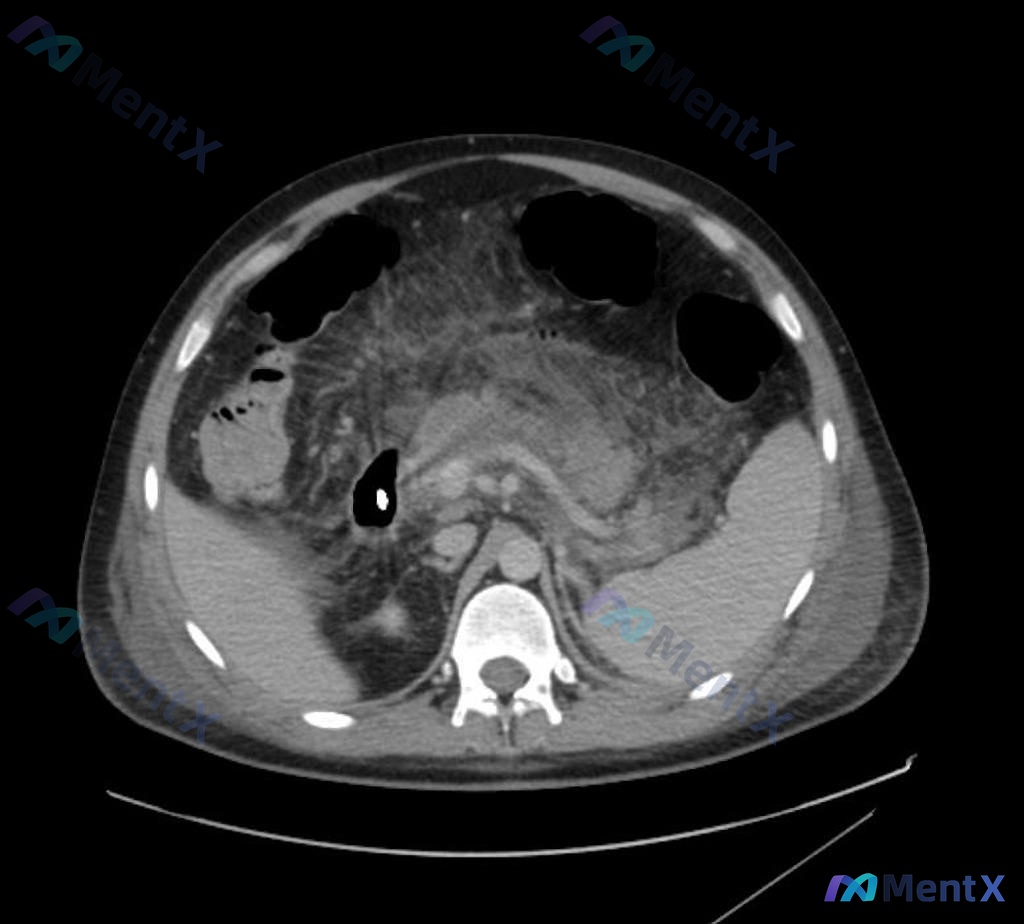

整理了一份急腹症的病例资料,想和大家重点讨论影像判断这块: > 基本情况:男性,既往胆结石十余年、高血压病史5年 > 主诉与体征:腹痛、腹胀,压痛、反跳痛阳性,体温38℃ > 实验室:血清淀粉酶1950U 目前临床倾向先按急性胰腺炎收治,但因为有腹膜刺激征和发热,需要影像上明确有没有坏死。 想先问两...

看到一个急腹症的病例资料,影像报告首先指向了急性胰腺炎,但越看越觉得哪里不对,整理一下思路和大家分享。 病例影像核心表现 先把影像里的关键信息理一理: - 胰腺:胰头及胰体明显肿大,密度不均,边缘模糊;主胰管扩张;胰周脂肪间隙广泛渗出、条索影。 - 胰周/腹膜后:腹主动脉前方、右侧肾周前方也有炎性渗...